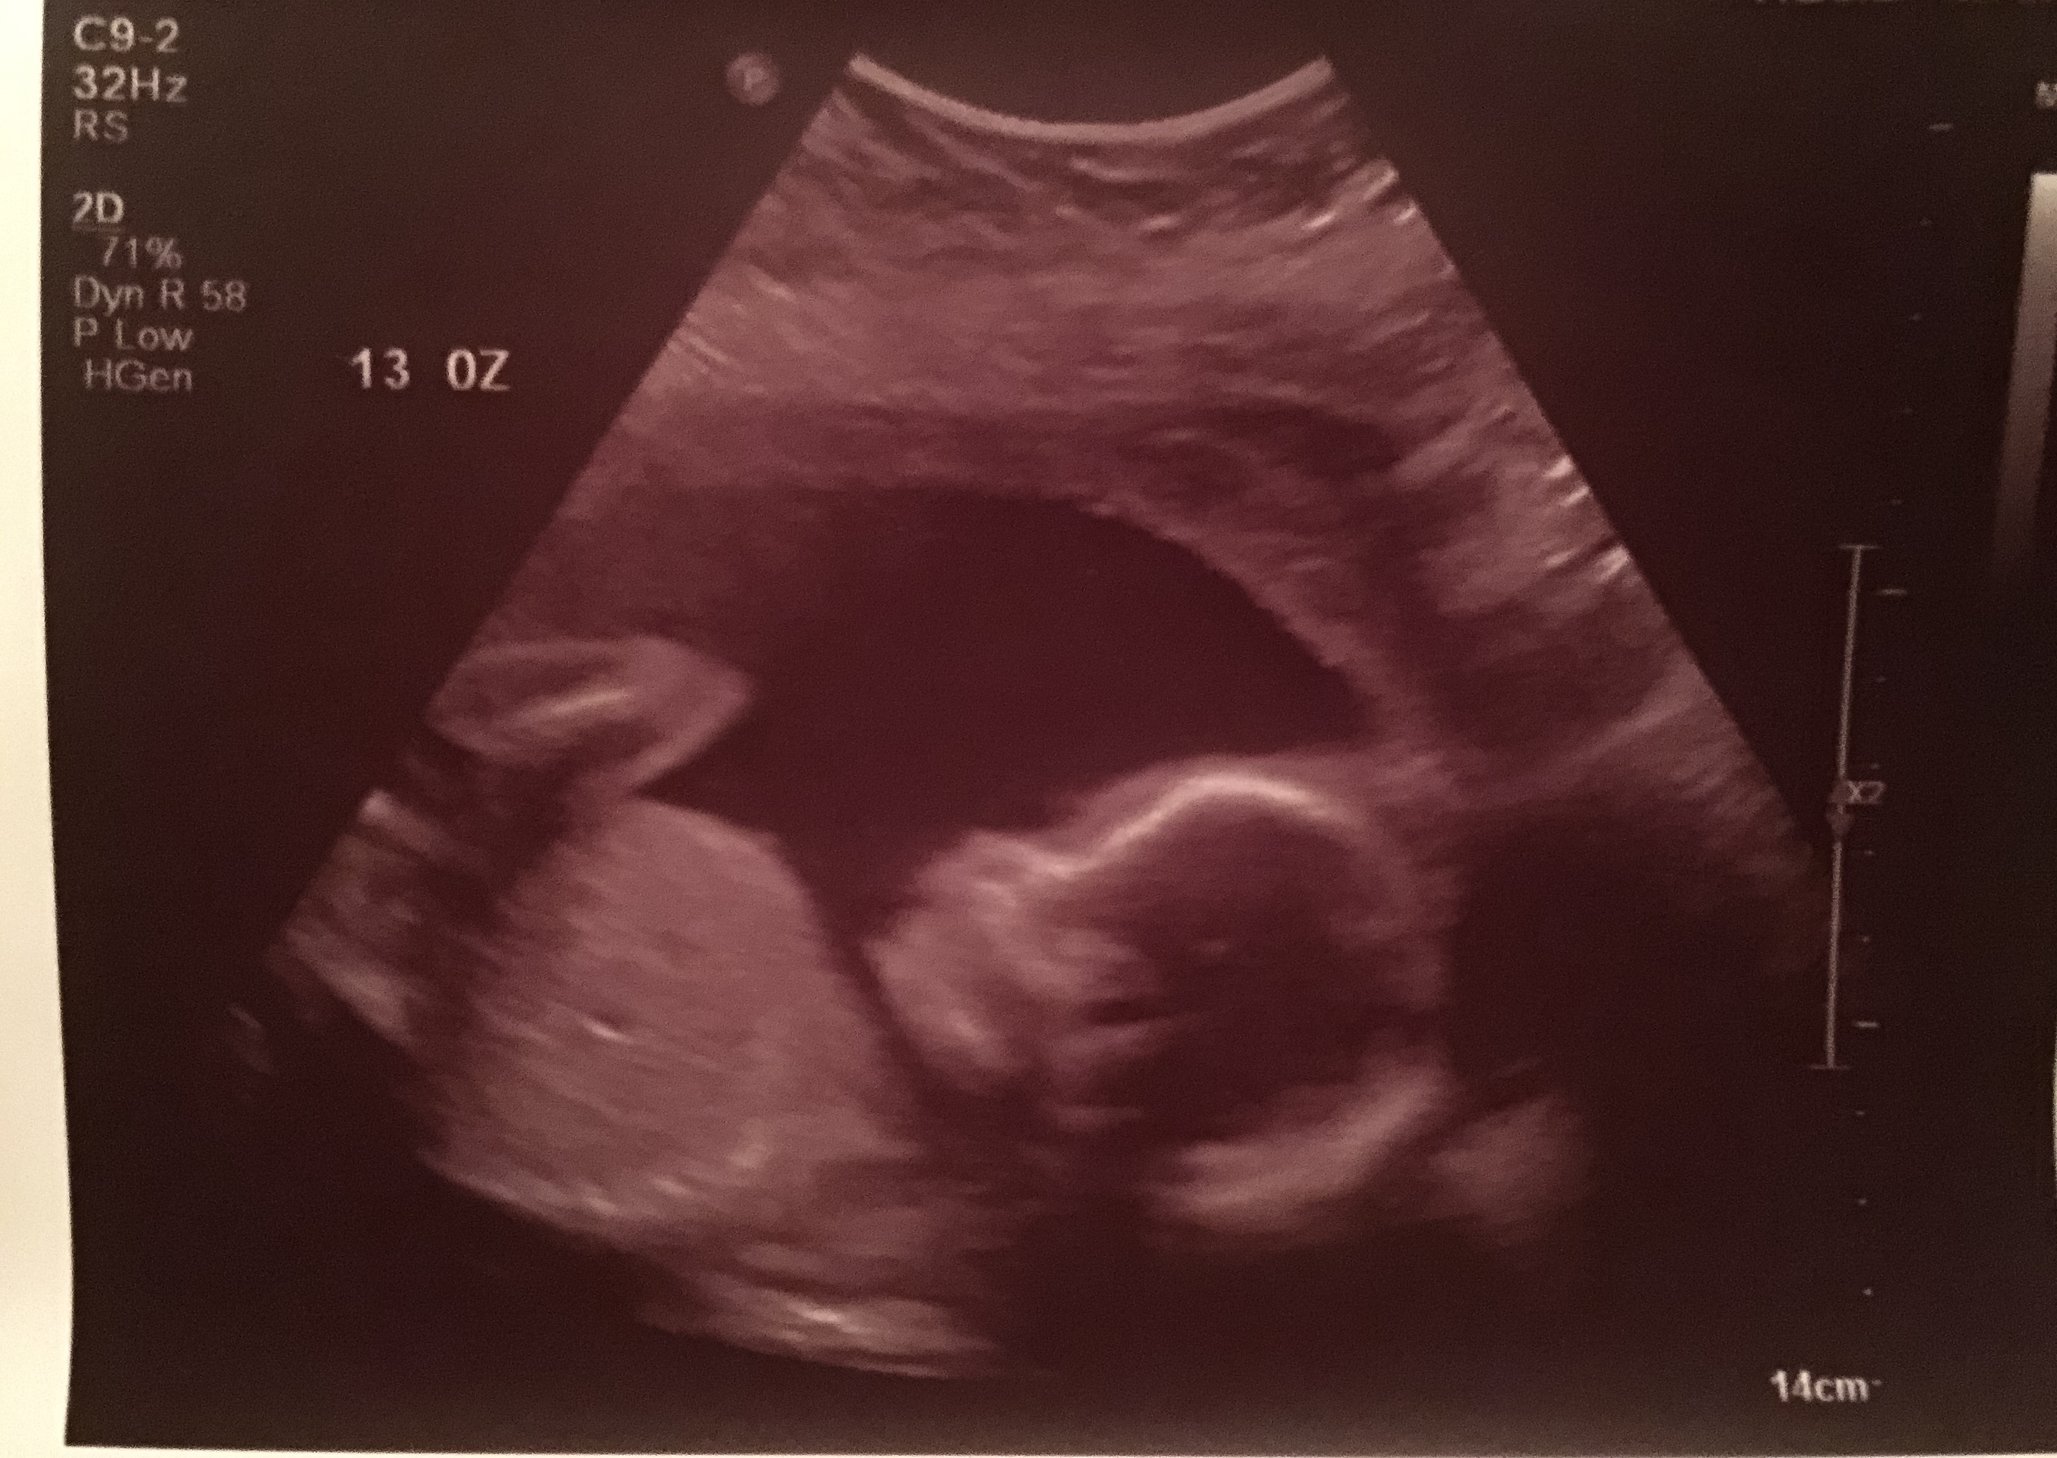

Concerning results from our 20 week scan today- update! 01-29-2016

• Hoping your appointment went well! I just found out today my LO has the CP cysts as well and we need to follow up with the Level 2 ultrasound. Keep us posted and I'll keep sending t&p your way!

• @RNMegan0711 what wonderful news! Thank you for sharing your update!!! Continued thoughts & prayers your way as you await your test results but so glad to hear everything looked perfect!!!

• Good news so far! Hoping Qnatal results show all is well with your baby girl. Hugs, lady!